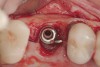

(6.) A 3.6-mm diameter implant was removed with a 4.0-mm diameter trephine drill. The apical portion of the implant was luxated carefully to preserve as much bone as possible.

Figure 6

(7.) Because apical and lateral bone volume was preserved with use of an ultrathin trephine, a wider diameter, 4.2-mm implant was placed at the time of implant removal. Bone augmentation was performed, and submerged healing was selected.

Figure 7